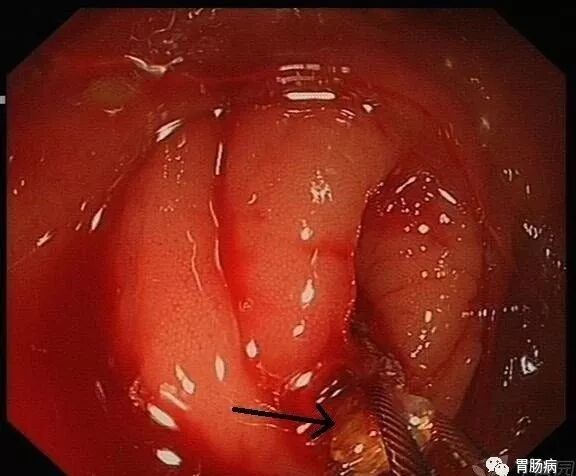

通过内镜前端的透明帽的帮助下,推开Gerlach’s瓣(黄箭头),并进行阑尾腔插管。

通过内镜下置入球囊导管或取石网篮,将粪石取出,原理如ERCP取石术。(黑箭头示取出的粪石)。